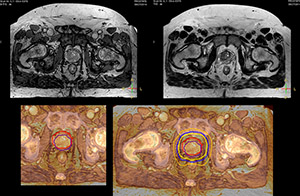

Impressive clinical benefits for prostate

“The biggest problem for CT-based planning, especially in prostate, is you can’t see the cancer very well,” says Dr. Stevens. “On CT it can be quite challenging to see the edge of the prostate especially at the apex. When the edge of the prostate can’t be delineated well on CT, radiation oncologists will increase their margins a little bit so they don’t miss it, but that can also increase toxicity.” “Using MR, the prostate is well delineated. We quickly see the edges of cancerous tumors like in prostate cancer, and as normal structures can be defined, we can optimize the treatment plan to protect these organs and their normal function. This can potentially improve the outcome. And it improves workflow as well. We can contour more quickly, confident that the tumor is going to be in the field.” “The Ingenia 3.0T MR scanner provides high resolution allowing us to make scans fast for the patients. It also gives the potential to include methods like MR spectroscopy and diffusion weighted Imaging, which we’re in the process of doing right now,” Dr. Stevens adds.